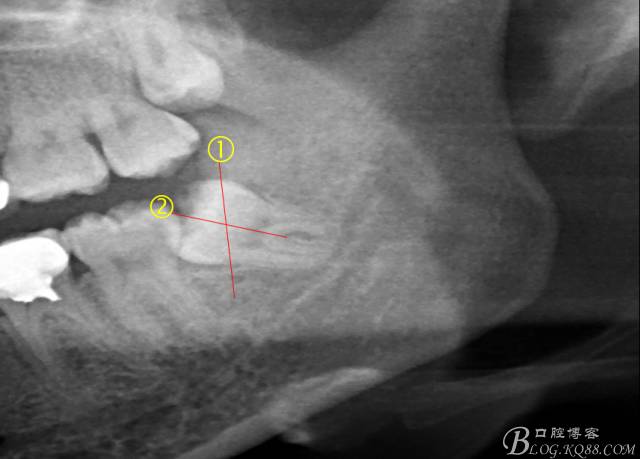

先分析智齒的情況,口內(nèi)直觀是半個(gè)牙尖都沒(méi)露出來(lái),差一點(diǎn)就完全埋伏了。磨牙后墊的可操作面積中規(guī)中紀(jì),X全景片示三類阻生,根冠比例是1:1,非融合根,近中根壓下頜管。

術(shù)前分析:智齒分牙的方法不少,但個(gè)人感覺(jué)都與這十字分牙法差不多,大多數(shù)阻生齒的分牙都在此基礎(chǔ)上進(jìn)行改進(jìn)。

計(jì)劃總趕不上變化,何況是充滿變異的智齒。由于可操作空間較小,原來(lái)計(jì)劃?rùn)M向分根改成矢狀分根。